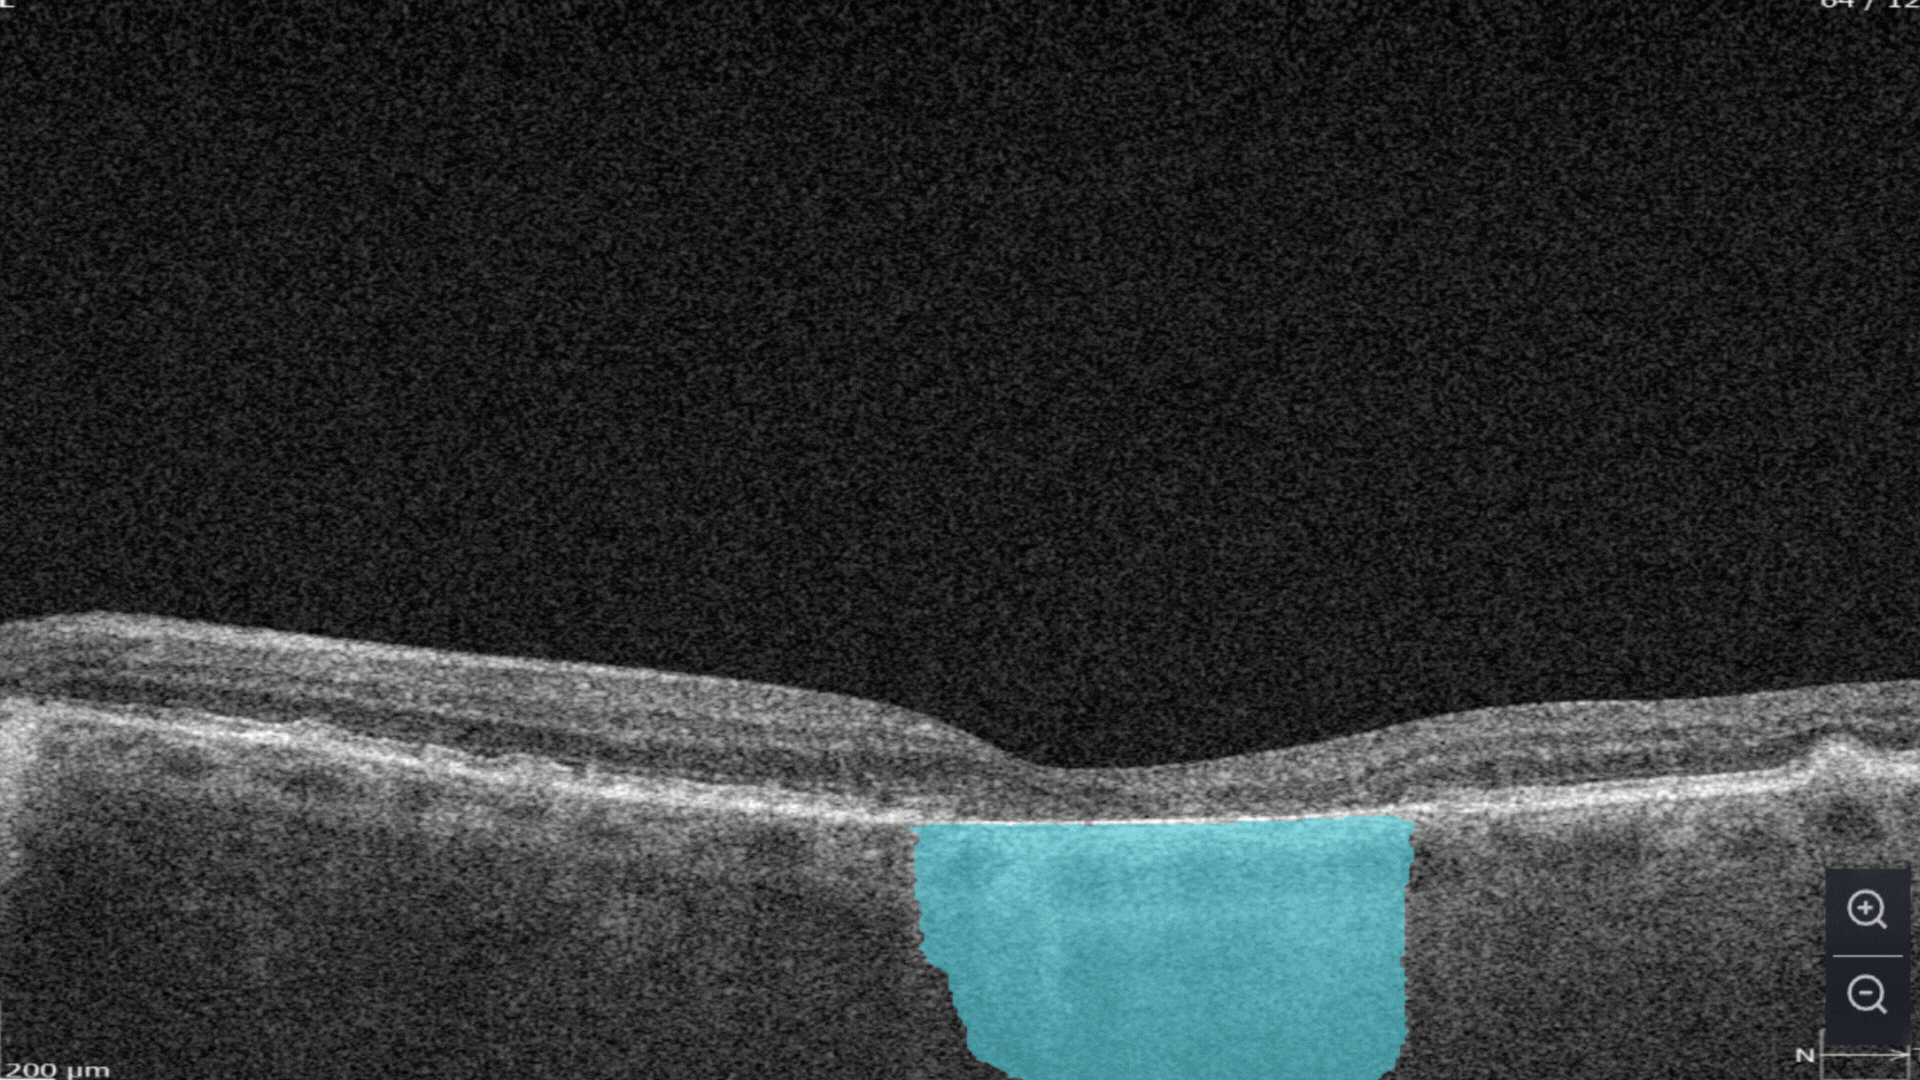

Subretinal fluid corresponds to the accumulation of a clear or lipid-rich exudate (serous fluid) in the subretinal space, i.e., between the neurosensory retina (NSR) and the underlying retinal pigment epithelium (RPE), in the absence of retinal breaks, tears, or traction

Fibrovascular RPE detachment. Delamination of the pigment epithelium of the retina is caused by the presence of newly formed vessels (fibrovascular membrane) under the RPE.

Subretinal hyperreflective material (SHRM). It’s a hyperreflective material that is external to the retina and internal to the retinal pigment epithelium (RPE)